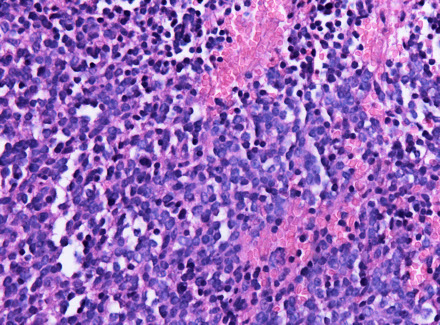

In the most primitive end of pineal neoplastic spectrum, comprising a small-round blue cell tumor with small rosettes (not the large "pineocytomatous" of benign tumors)

Lots of mits, inc Ki67; (+) synapto and NFP

Pineoblastoma